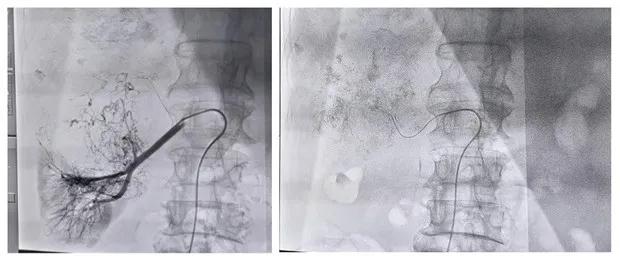

明确诊断后,经科室讨论考虑,患者为肿瘤晚期,失去外科手术机会,经肝动脉及肾动脉栓塞化疗是目前治疗不能手术切除肿瘤的最好治疗方法。经与患方充分沟通后,给予行肝动脉及右肾动脉栓塞化疗术,手术顺利,术后患者恢复良好。

经动脉栓塞是阻断肿瘤的供血动脉,切断肿瘤细胞的营养供应,达到饿死肿瘤细胞的目的;同时给予肿瘤供血动脉灌注化疗,化疗药物浓度高,是常规静脉化疗药物浓度的1000倍,可有效杀死肿瘤细胞。